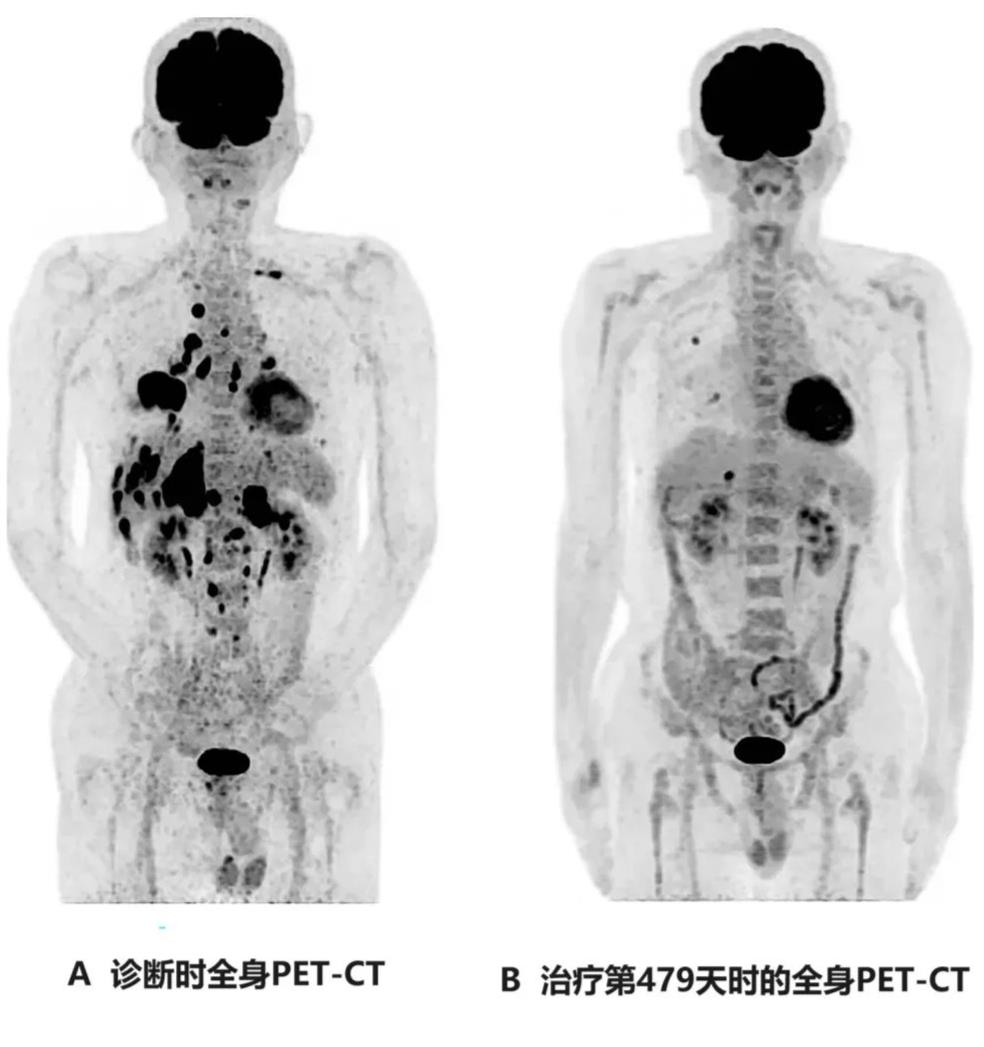

4、全身PET-CT:治疗后第479天,复查全身PET-CT显示,除肝脏转移灶(直径1.7cm)、右肺转移灶(直径1.0cm)外,未见其他异常表现(详见下图)。

图 该患者治疗前后全身PET-CT对比

▲图源“Cureus”,版权归原作者所有,如无意中侵犯了知识产权,请联系我们删除

注:

图A:示右下肺原发肿瘤,伴多发性肝转移、多发性双侧肺内转移、多发性骨转移、双侧肾上腺转移。

图B:示肝脏可见1个小转移灶(直径约1.7cm),右肺见2个小转移灶(直径约1.0cm)。